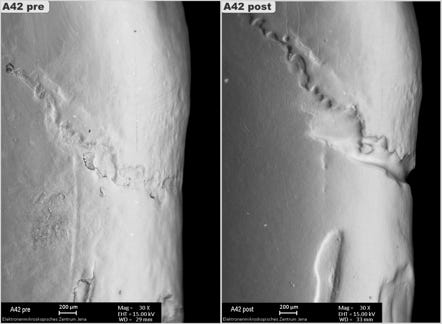

Toothbrushes and toothpaste play a crucial role in oral health. Their design and composition can significantly impact the rate and pattern of tooth wear. The ORMED methodology of clinical simulation of cervical wear by robot simulated 3-year toothbrushing in a human tooth model is the most sophisticated test model to answer this research question.  It plays a major role in innovating and improving toothbrushes and dentifrice to balance the effect of plaque control and oral hygiene by minimizing the effect of severe tooth wear.